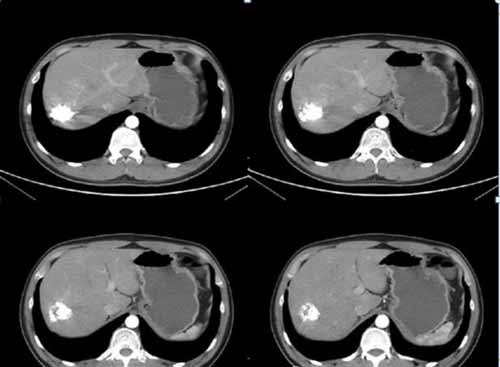

(術(shù)后復(fù)查肝血管瘤固縮,栓塞劑沉積良好,無復(fù)發(fā))